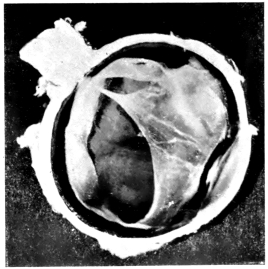

PLATE II.

FACING

PAGE

10.

LENS DISLOCATED BETWEEN CILIARY BODY AND SCLERA

curly bracket span

11.

NUCLEUS OF CATARACT FREELY MOVABLE BETWEEN THE AQUEOUS AND VITREOUS CHAMBERS

12.

LENS IMPACTED IN ANGLE OF ANTERIOR CHAMBER

13.

CAPSULE OF MORGAGNIAN CATARACT IMPACTED IN ANGLE OF ANTERIOR CHAMBER

14.

LENS FLOATING FREE IN VITREOUS CHAMBER

15.

LENS LIGHTLY IMPRISONED IN EXUDATE INTO VITREOUS CAVITY